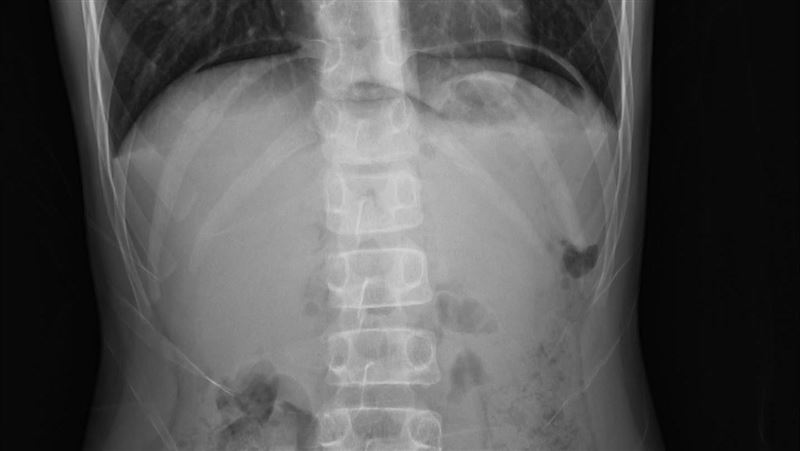

▲女童照腹部X光,發現雙側橫隔膜看到明顯的free air(游離空氣),診斷為胃潰瘍穿孔。(圖/翻攝自「Dr. E 小兒急診室日誌」臉書)

謝宗學隨後交代住院醫師帶女童去照腹部X光,結果如他預期,「以在雙側橫隔膜看到明顯的free air(游離空氣),診斷應該是胃或十二指腸穿孔。」於是他趕緊聯絡小兒外科醫師,同時安排腹部電腦斷層掃描做最後確認,女童在最短的時間內接受適合的手術,再經過數天住院治療後,恢復健康。